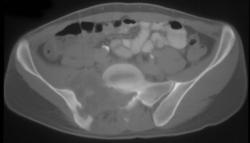

3D of Ampato Mummy With Skull Fracture - Incan Mummy